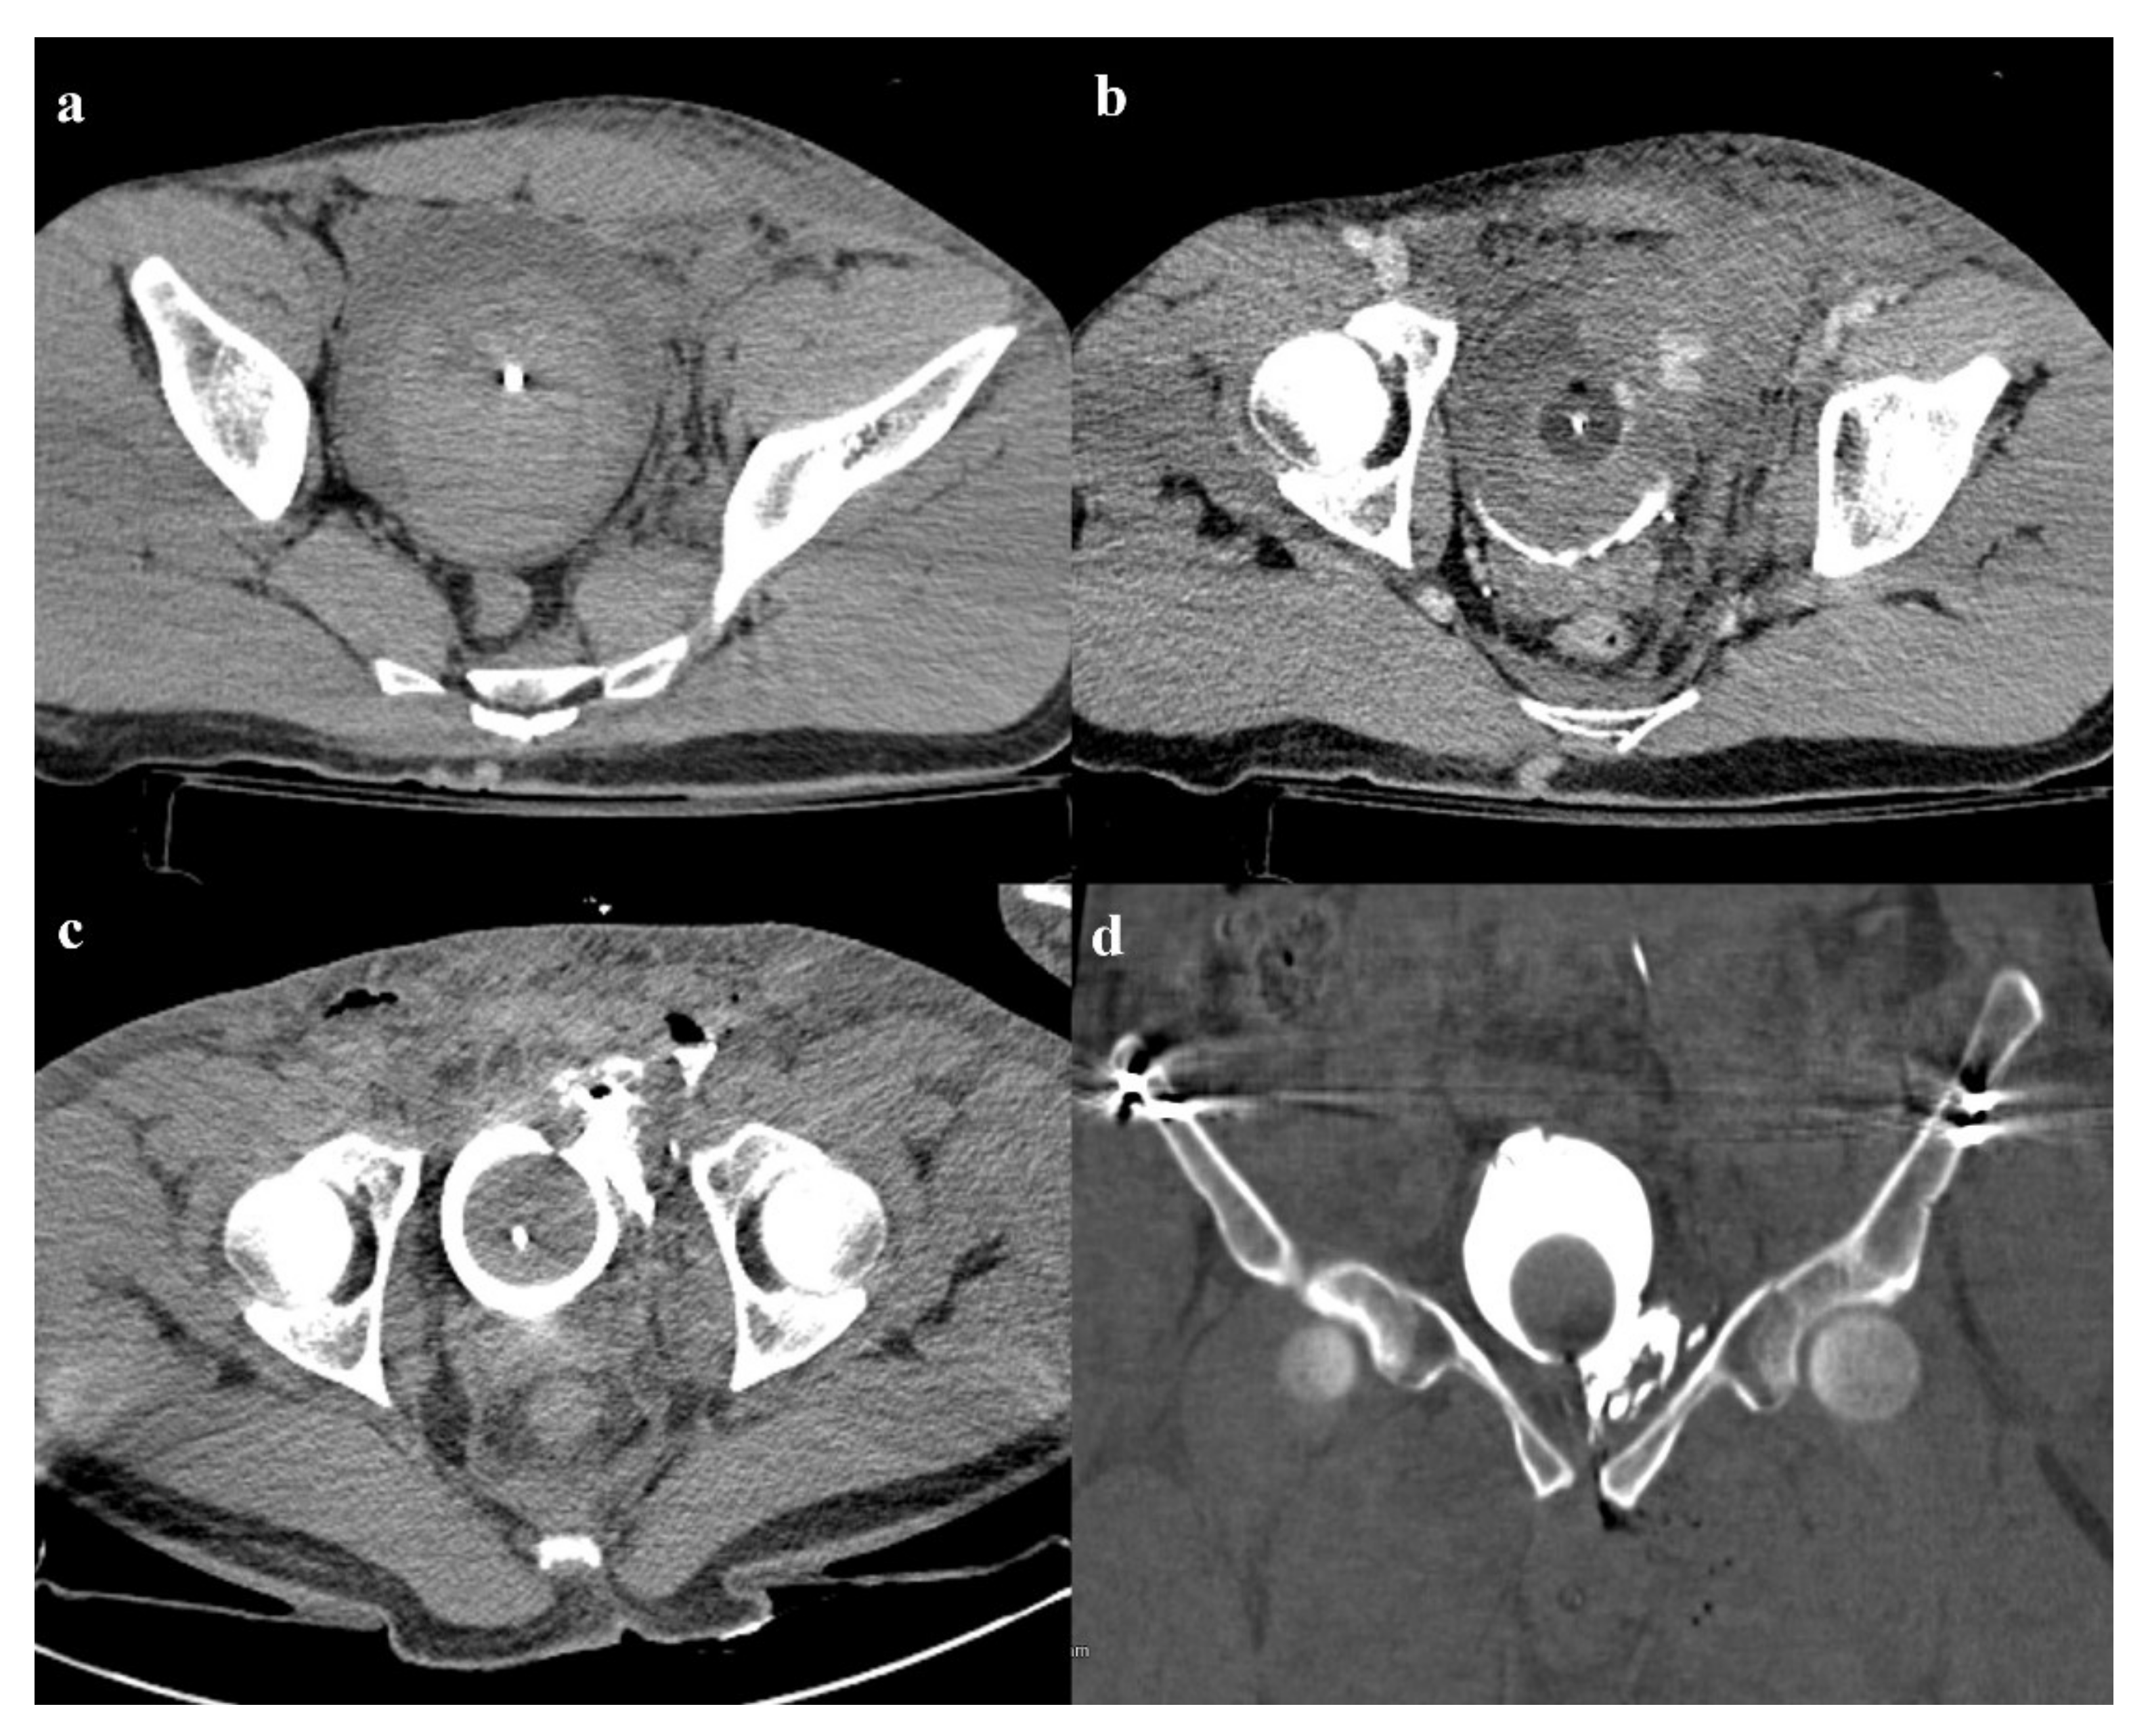

There are four types of bladder injuries: contusion, intraperitoneal rupture, extraperitoneal rupture, and combined rupture [58]. Extraperitoneal rupture is the most common bladder injury (80–90% of cases) in association with anterior pelvic ring fractures and is treated conservatively [59]. On the other end, intraperitoneal rupture is rare and has a surgical treatment [60].

In the evaluation of bladder lesions, the most accepted diagnostic tool is CT cystography with the retrograde introduction of 300 mL of diluted water-soluble iodinated contrast medium [61,62]. The retrograde approach allows the detection of any bladder rupture, through contrast extravasation in the perivesical space or in the peritoneal space (Figure 12).

Figure 12. Patient of the Figure 5, with an anterior–posterior compression fracture. There is a large hematoma inside the bladder (a); contrast medium administration reveals active bleeding in the venous phase of the examination, on the left wall of the bladder (b). Axial and coronal CT cystography images show a leak of contrast medium in the perivesical space, suggestive of extraperitoneal bladder rupture (c,d).